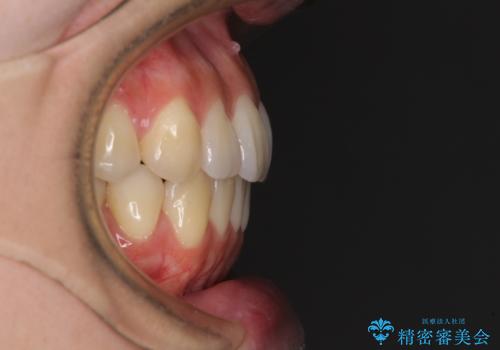

オープンバイトでかみにくい インビザラインによる矯正治療

上下の奥歯を圧下させるようにすることで、前歯を接触させるように計画しました。

上下の隙間に舌が入り込むことがオープンバイトの原因であったため、舌の筋肉のトレーニングも並行して行い、後戻りの抑制を図りました。